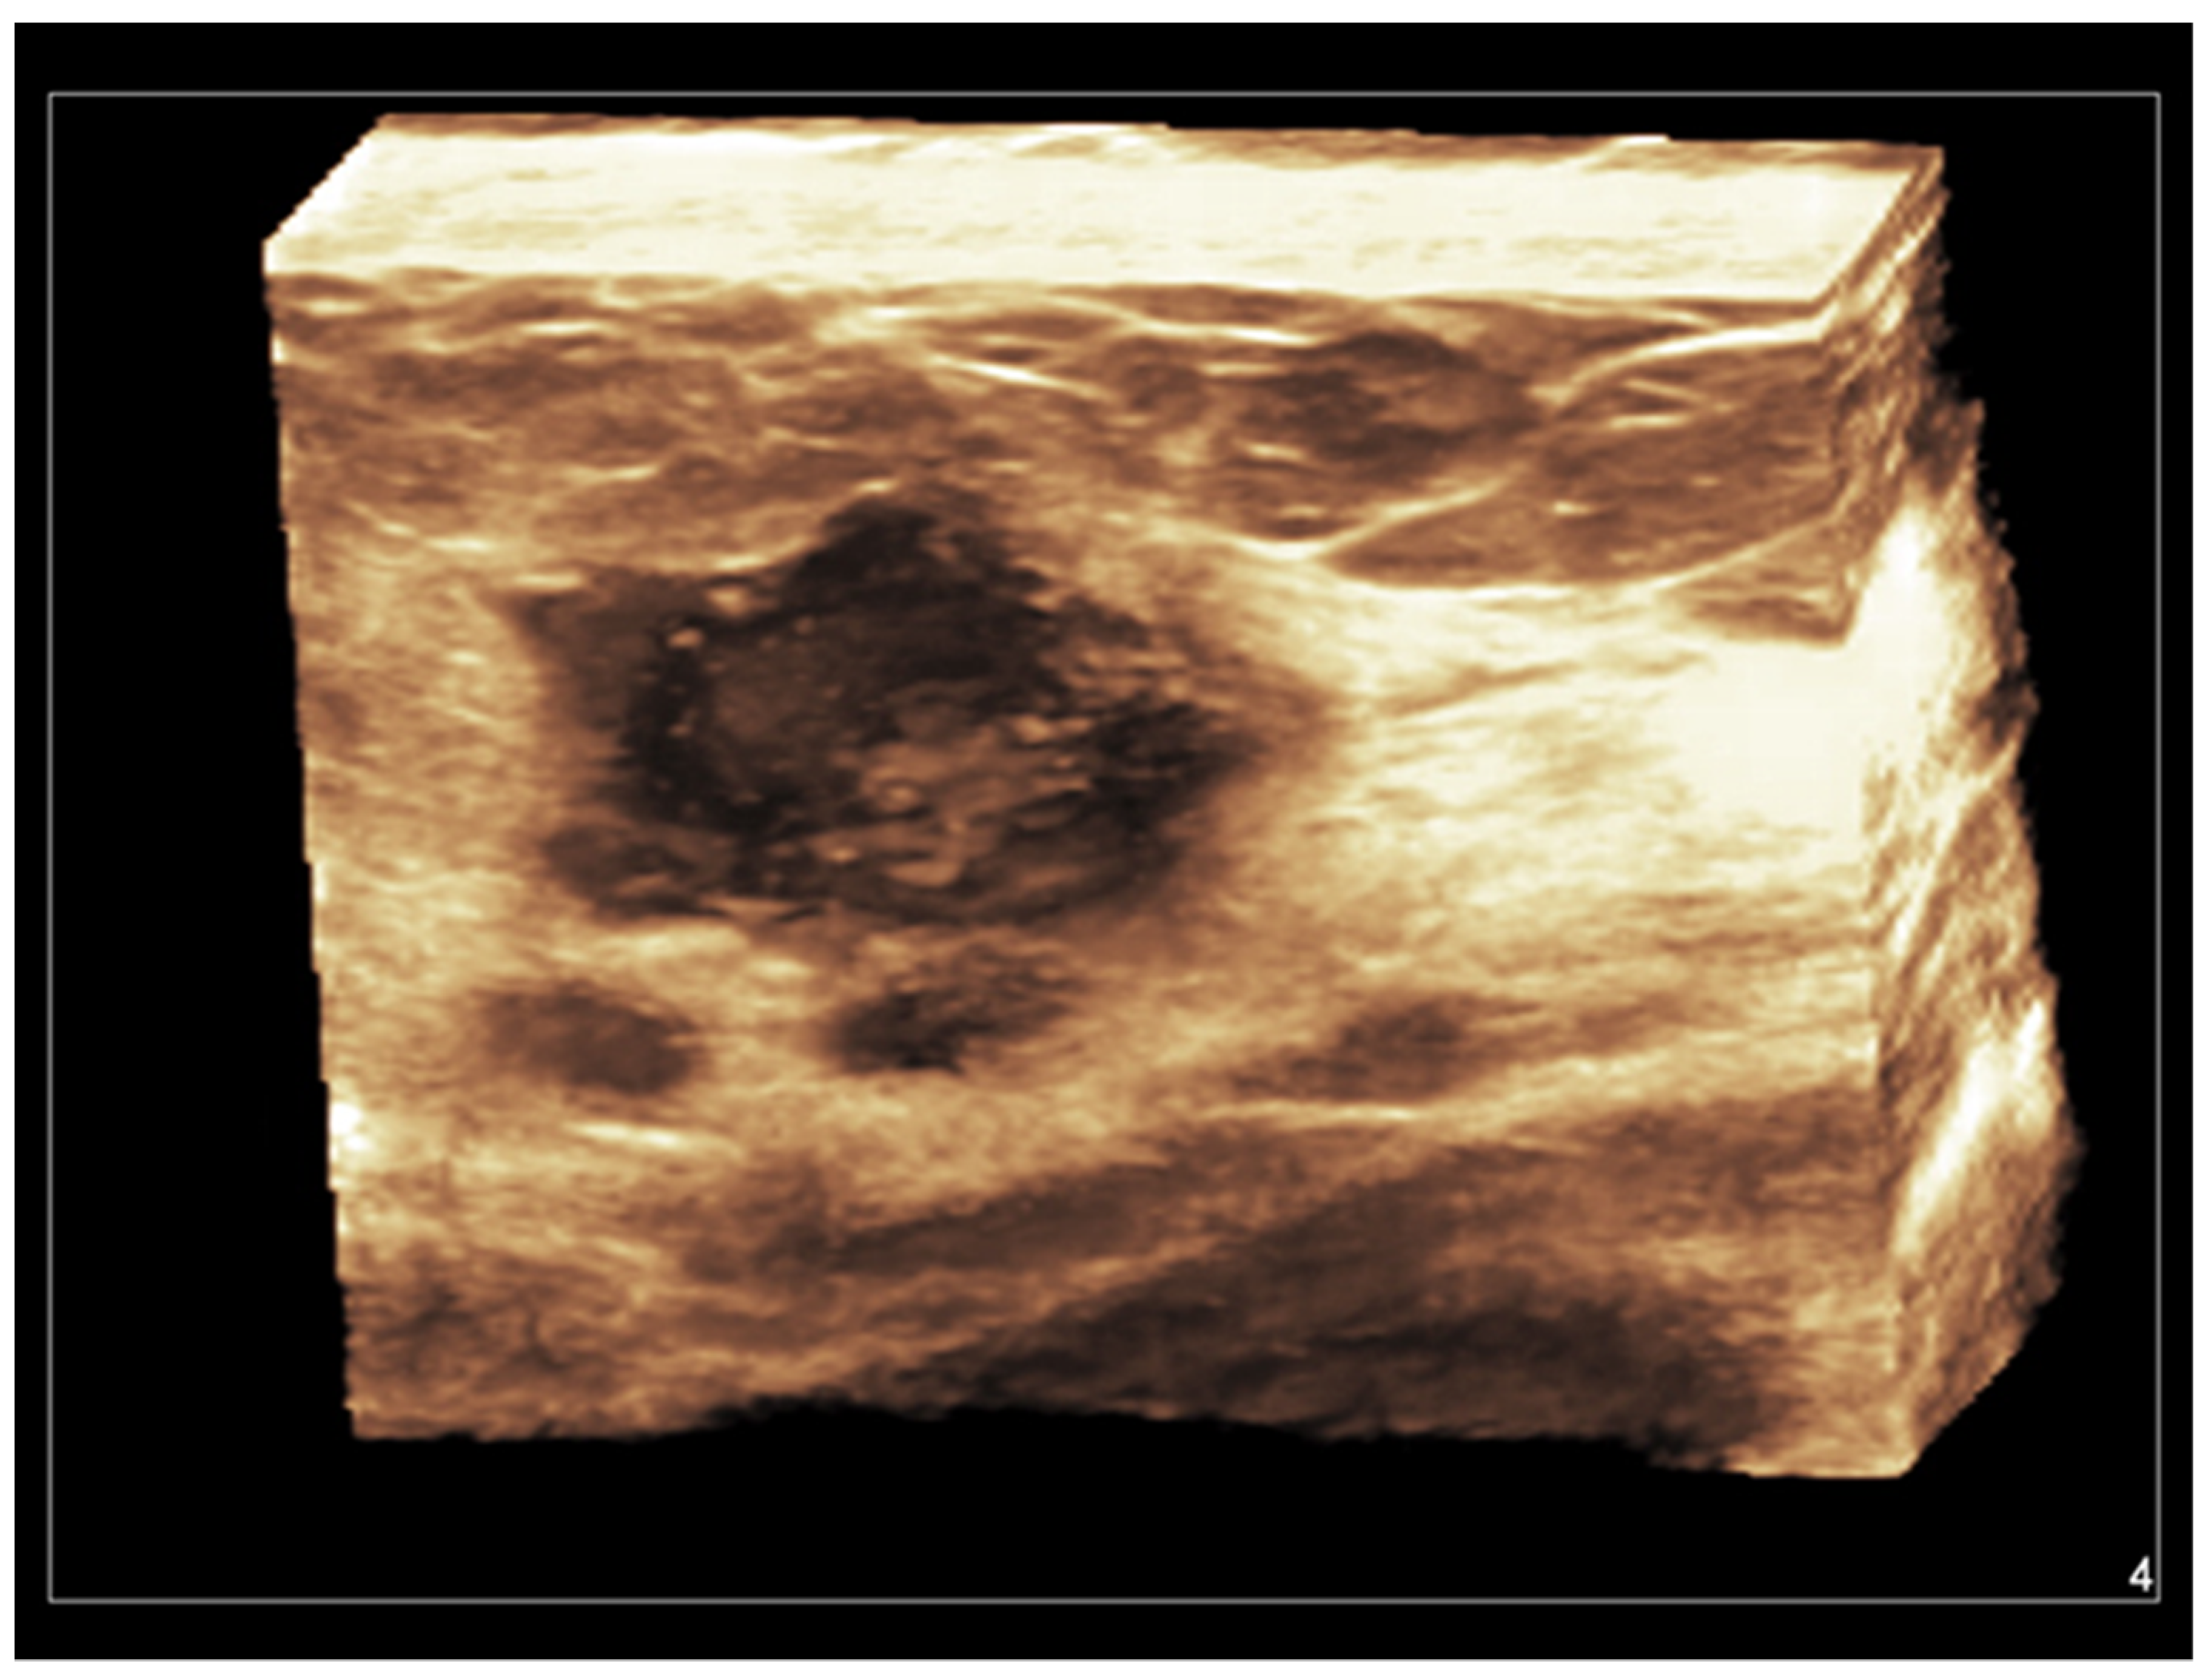

Both hand-held and automated linear transducers are available for use in high-resolution 3D breast imaging. Three-dimensional US, also called volumetric US, allows for obtaining a surface rendering of normal and abnormal breast structures. With a single pass of the ultrasound beam, a 3D reconstructed image is formed in the coronal, sagittal, and transverse planes, allowing a more accurate assessment of anatomical structures and tumor margins [11]. Coronal images, being parallel to the skin, represent a unique opportunity allowed from 3D US. A vivid representation of breast tumors can be obtained, with a retraction, star-like profile strongly supporting the diagnosis of malignancy [70,71,72,73,74] (Figure 5).

Figure 5. Invasive ductal carcinoma of the breast. Coronal 3D display of infiltrating tumor margins.